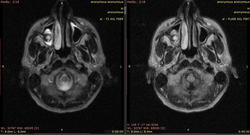

Мужчина 38 лет, жалуется на головную боль головокружение. На МРТ определяются изменения в мозжечке, стволе головного мозга и верхнечелюстных пазухах... Наркотики, ВИЧ отрицает... ДАЙКОМ

Видны изменения в стволе мозга (мост), белом веществе мозжечка и, помимо этого, белом веществе большого мозга (виден по крайней мере один перивентрикулярный очаг в левой теменной доле, нельзя исключить более мелких очагов - трудно судить по низкопольным картинкам).

Такая картина характерна для центрального понтинного миелинолиза. Он возникает в основном у алкоголиков на фоне острый осмотических нарушений. При этом поражается в основном мост, но также могут быть видны очаги в других отделах мозга (экстрапонтинный миелинолиз). Поэтому и понтинные, и экстрапонтинные изменения объединяются термином "синдром осмотической демиелинизации". Вот здесь разные случаи: http://radiopaedia.org/articles/central-pontine-myelinolysis

Второй вариант, менее вероятный - первичное демиелинизирующее заболевание (РС).

В любом случае, я бы рекомендовал МРТ на высокопольном аппарате (какой у вас, 0,2 Тл?) с контрастным усилением, чтобы лучше визуализировать количество и локализацию очагов.